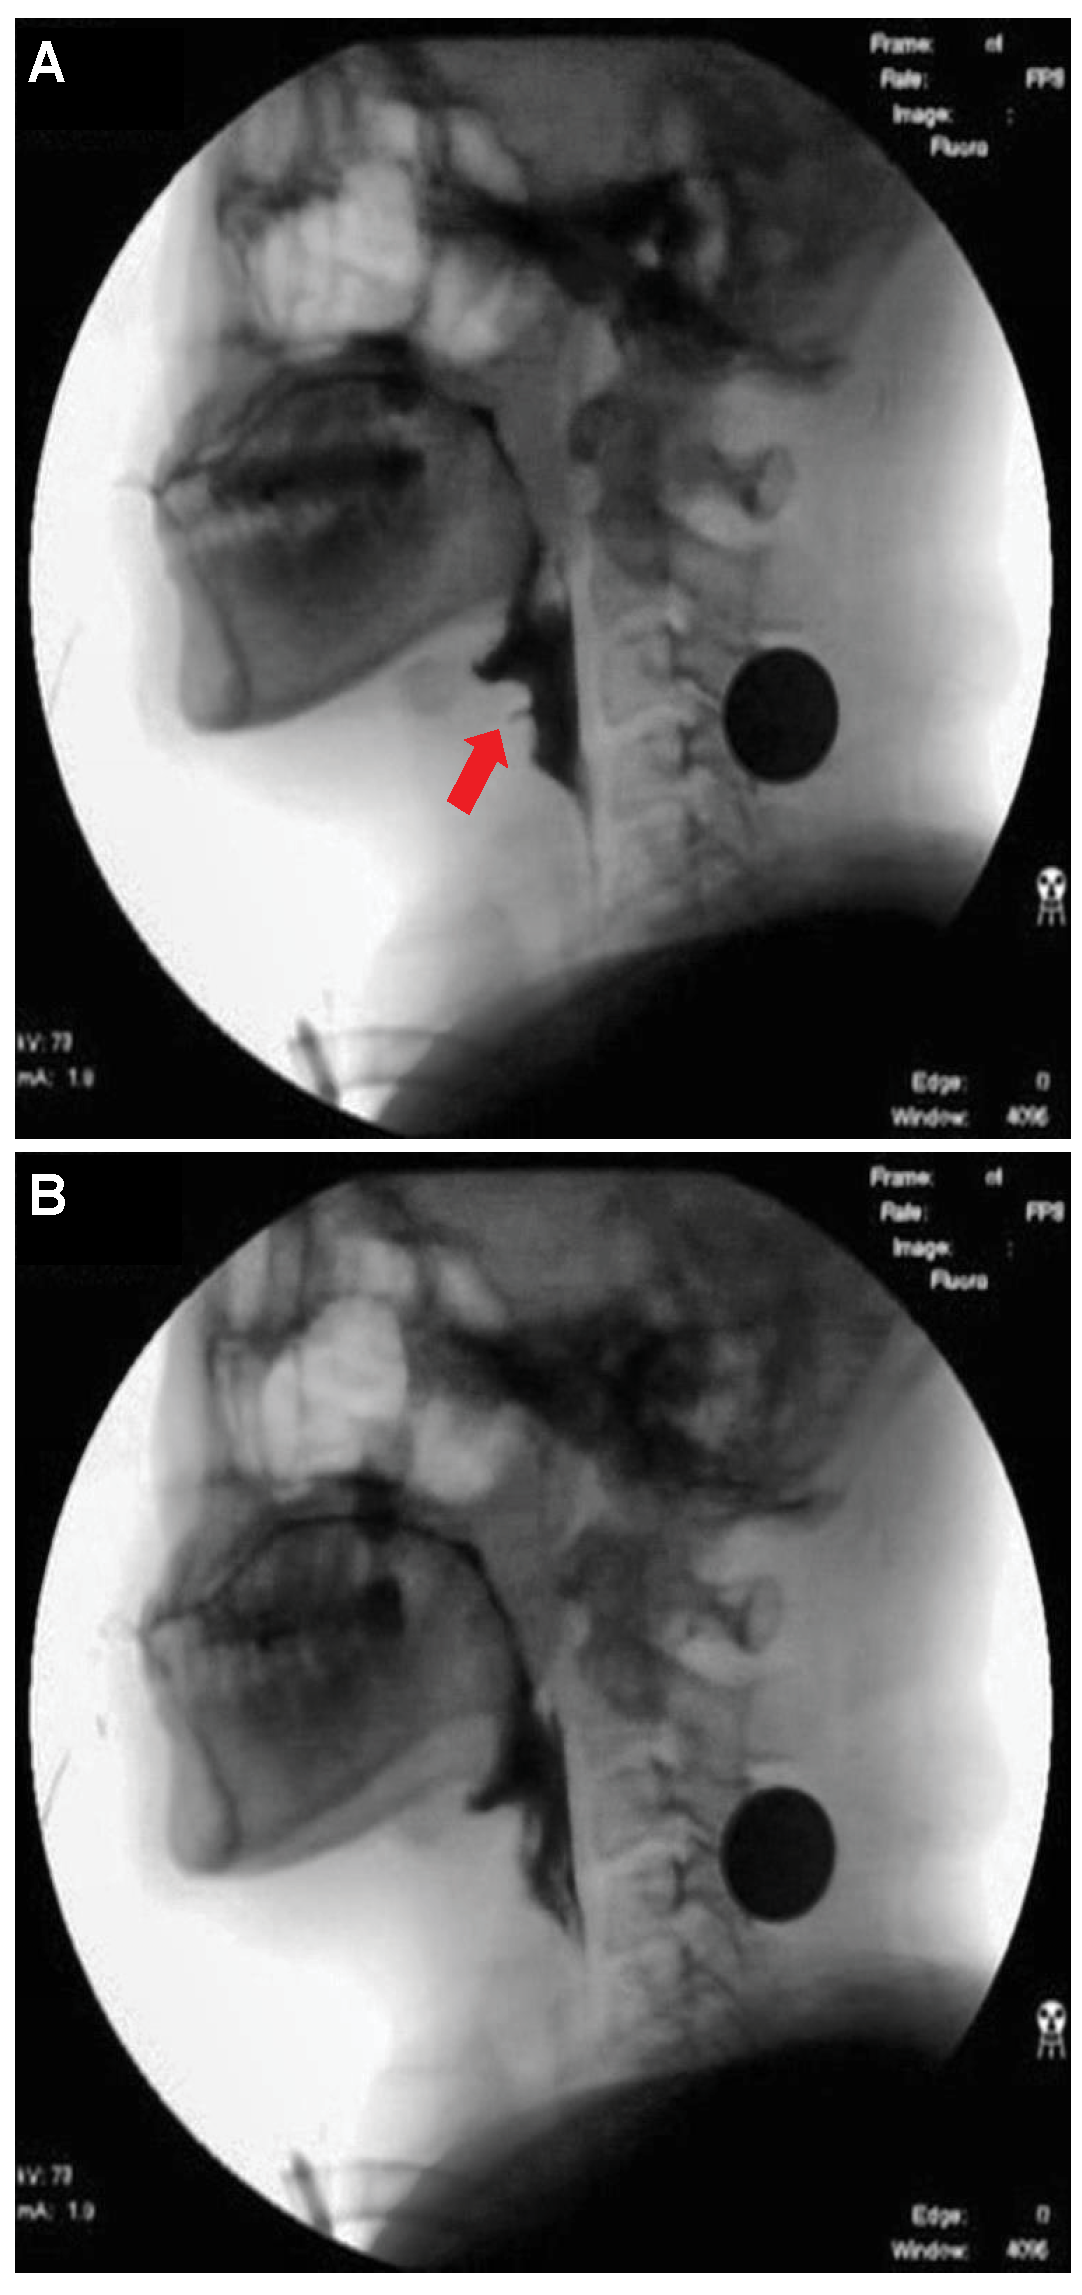

- Deep neural network for the detection of airway invasion:As described in Section 2.3.1, the ROI image (Figure 2C) specified using U-Net is used as the input image for airway invasion detection. To identify the occurrence of airway invasion in individual image frames, we designed a DCNN (deep convolutional neural network)-based classifier. Based on the position and shape of the bolus in the image, the classifier distinguishes whether the bolus is passing normally through the esophagus (normal swallowing action) or whether airway invasion has occurred.A deep neural network contains numerous connections between neurons, and a weight is assigned to each connection. The deeper the network is, the greater the number of weights to be learned, where this increase scales exponentially; consequently, sufficient data are needed to prevent overfitting. Therefore, among the models that can be effectively trained on limited data, in this paper, we choose a CNN based on an Xception module [27]. The Xception architecture not only reduces the number of parameters to be learned by performing convolution on each channel of the image, but also has the advantage of efficiently utilizing spatial and cross-channel correlations in the image (Figure 4). Additionally, by means of residual connections, the degradation problems that can occur as the network deepens can be avoided. In the Xception architecture, data are processed through three flows, namely (1) the entry flow, (2) the middle flow, and (3) the exit flow, and this architecture consists of convolutional layers with a total of 36 3 × 3 filters. All common convolutional and separable convolutional layers are followed by batch normalization [28].For airway invasion detection, we defined the image frames corresponding to instances of airway invasion as the positive class (Figure 5A) and the remaining image frames as the negative class (Figure 5B) and designed a CNN classifier using the Xception architecture with a binary output. Among the 15,335 positive image frames and 252,413 negative image frames included among all 319 video files, seventy percent of the videos in each class were used as training data, and ten percent were used for the validation of the trained network. The remaining 20% of the videos were used as test data to evaluate the final performance of the proposed classifier. Table 1 shows the total number of image frames used in the experiment and the numbers of frames in each class used for training, validation, and testing.In this study, we used an Xception module [27] pretrained on ImageNet and fine-tuned through transfer learning [25] on videofluoroscopic image data (Figure 4). The pretrained Xception module takes an image with 3 channels and dimensions of as the input, whereas a video fluoroscopic image is a grayscale image with a single channel. Therefore, we used the same grayscale ROI image resized to as the input to each of the three channels. The transfer learning procedure increased the validation accuracy by approximately 5% compared to training from scratch.